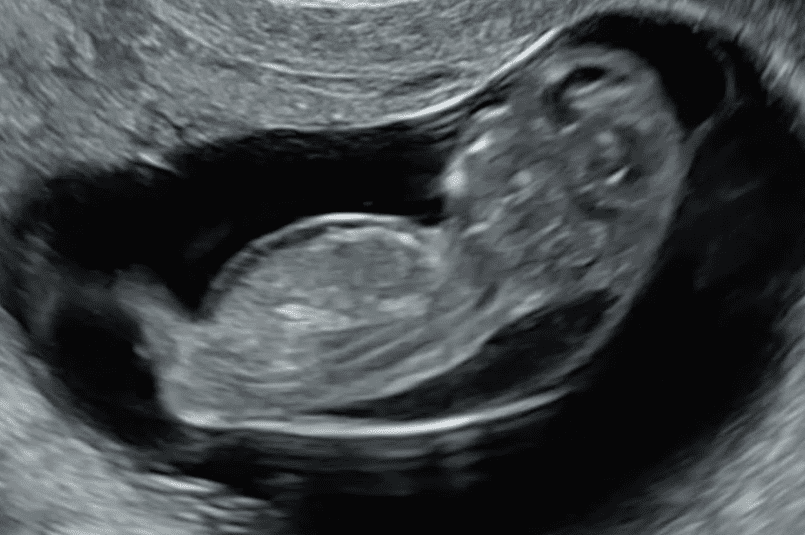

Lithopedion vakaları tıp tarihinde oldukça ilginç örneklerle kaydedilmiştir. Bazı kadınların bedeninde taş bebekler 50-60 yıl boyunca fark edilmeden kalabilmiştir. Çoğu zaman bu durum, tesadüfen yapılan radyolojik görüntülemeler sırasında ortaya çıkar. Tıbbi literatürde milyonlarca doğumda yalnızca birkaç vaka rapor edilmiştir, bu da sendromun ne kadar nadir olduğunu gösterir.

Taş Bebek Sendromu aslında insan bedeninin olağanüstü adaptasyon yeteneğini ortaya koyar. Ölü dokunun vücutta kalması ciddi enfeksiyon riski yaratabileceği için bağışıklık sistemi bu dokuyu kalsiyumla kaplayarak adeta “koruma altına” alır. Bu süreç, annenin sağlığını korumak için geliştirilmiş doğal bir savunma mekanizmasıdır.

Her ne kadar nadir görülse de lithopedion vakaları, gebelik sürecinin ne kadar hassas bir dengeye bağlı olduğunu hatırlatır. Tıbbi açıdan dramatik olduğu kadar ilginç bir olgu olan taş bebek sendromu, hem insan bedeninin sınırlarını hem de gebelikte erken teşhisin önemini vurgular. Ayrıca bu durum, kadınların yıllarca farkında olmadan bedenlerinde taşlaşmış bir gebelik taşıyabilmelerinin psikolojik etkileri açısından da dikkat çekicidir.